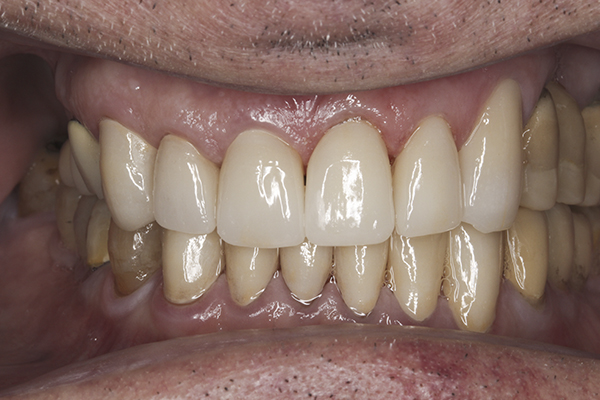

(36.) Postoperative anterior, closed view. Note the position of the upper and lower canines to provide canine guidance.

Figure 36